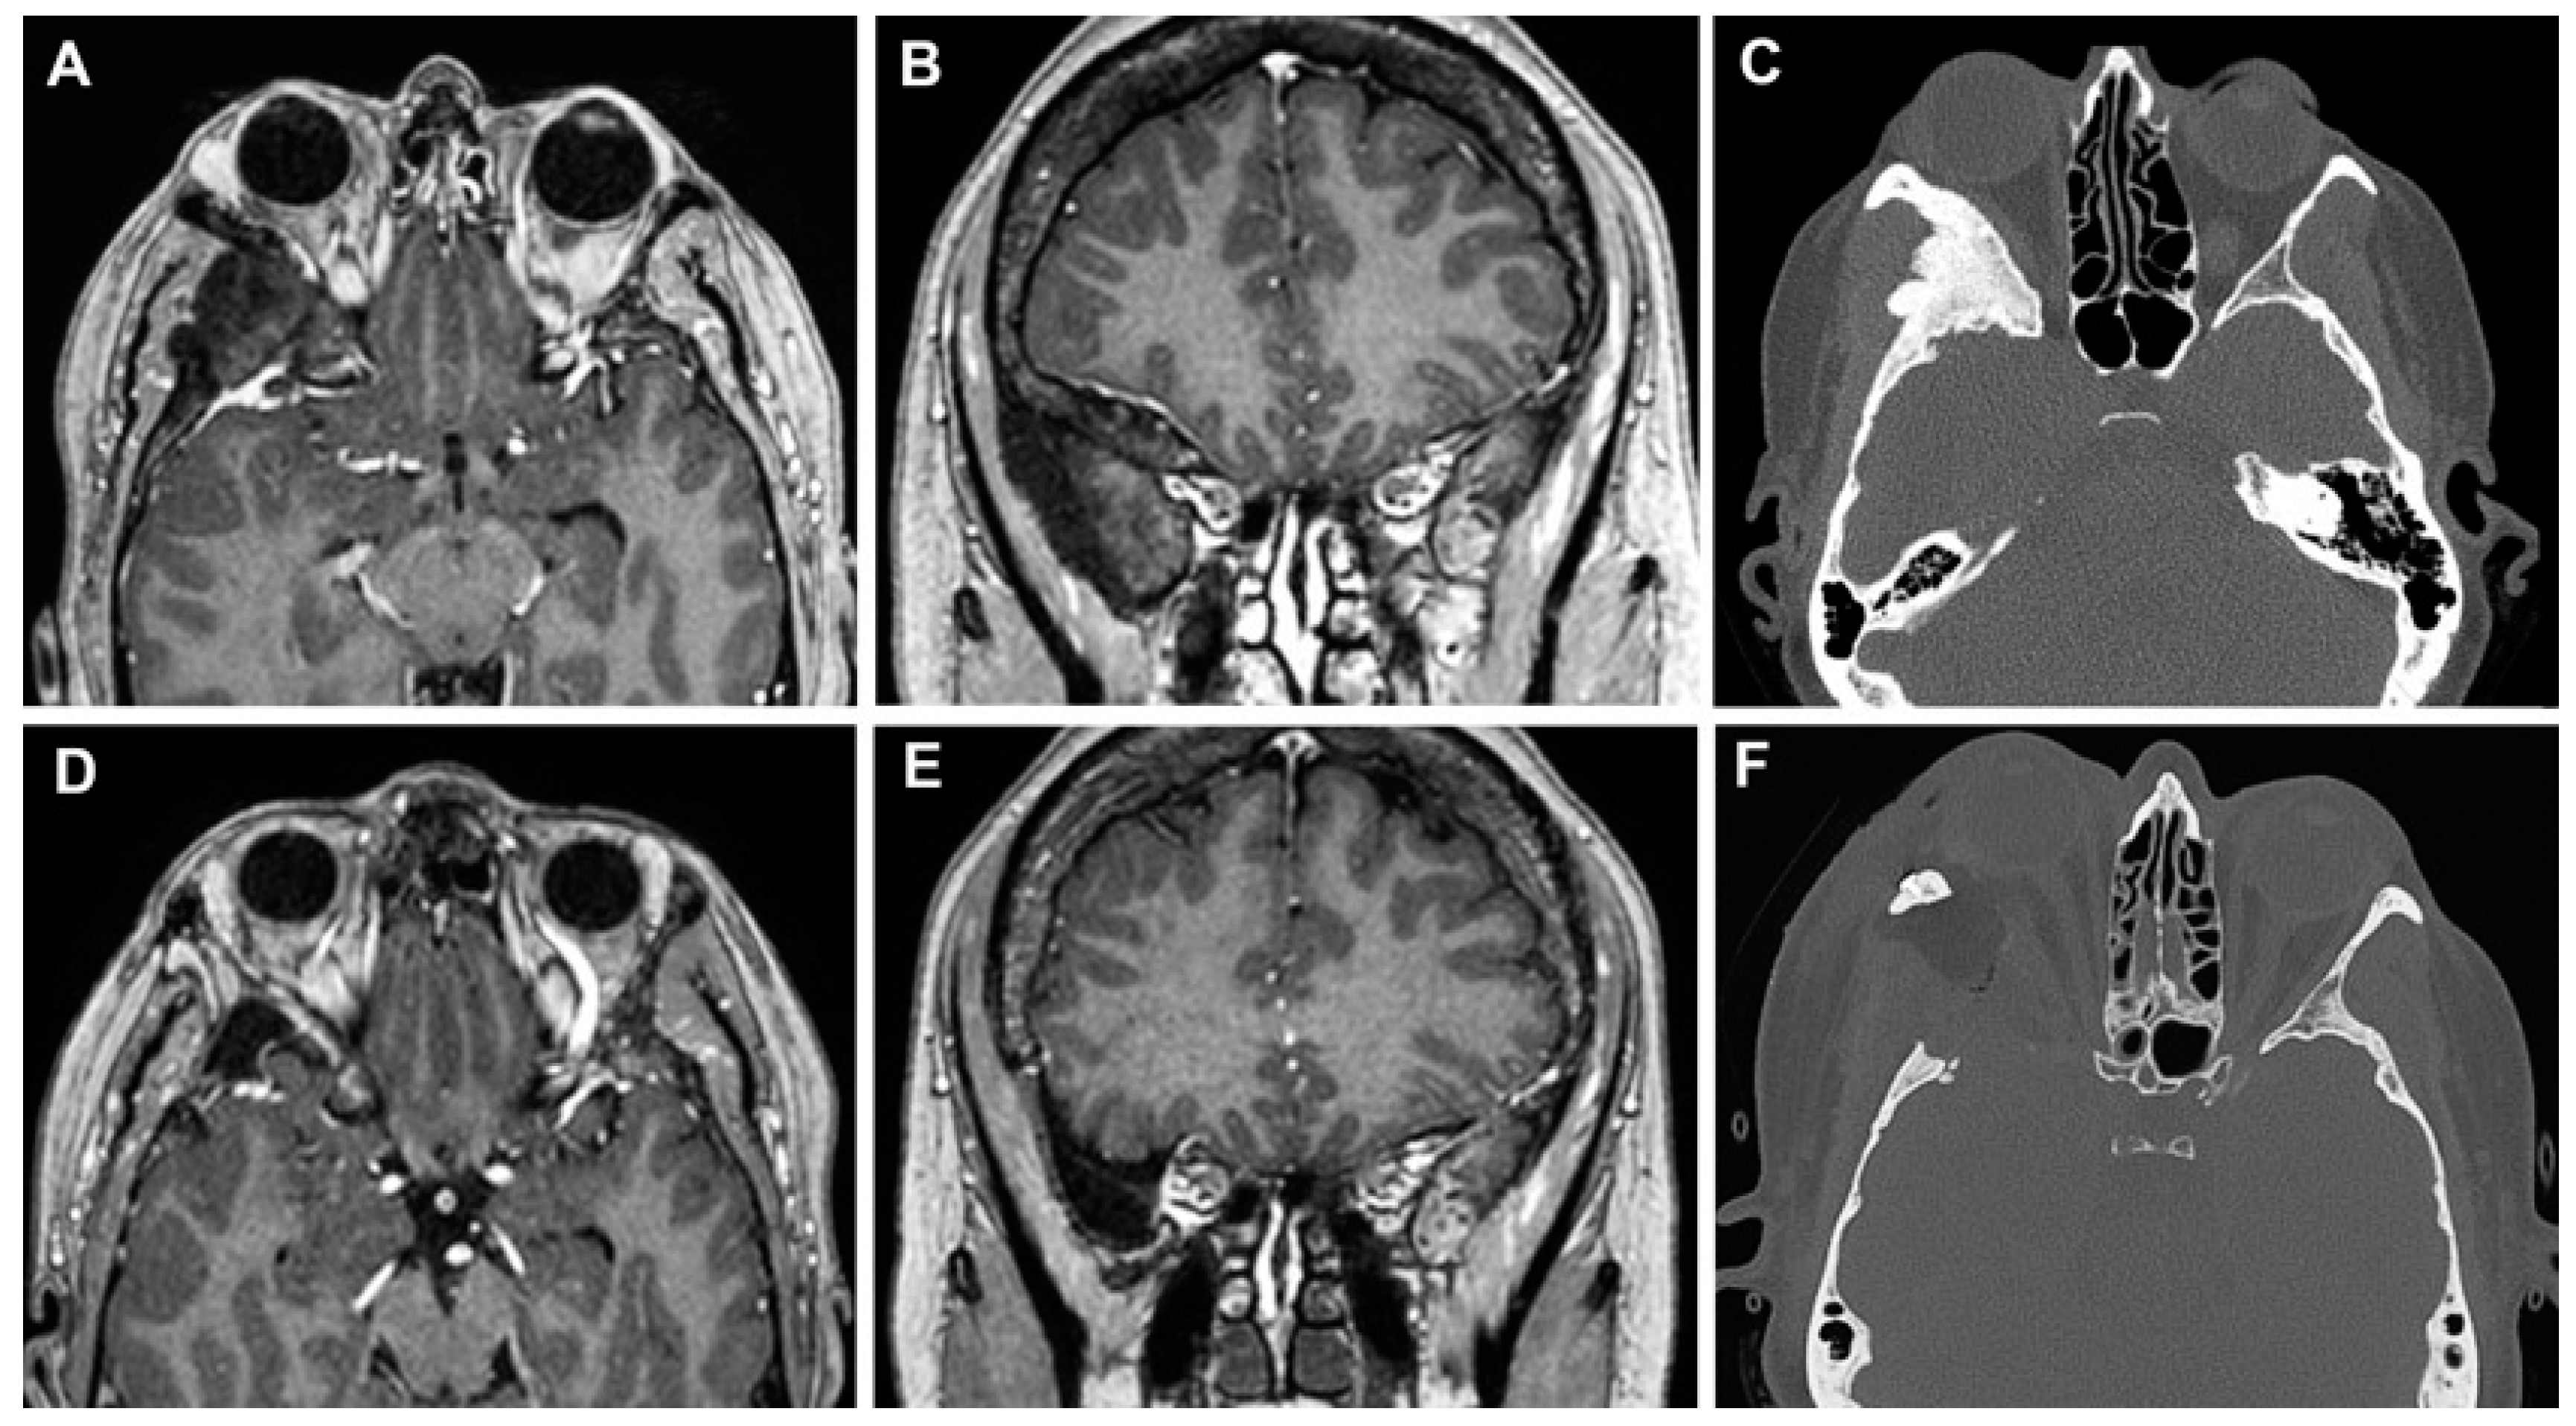

3.3. Clinical Cases

3.3.1. Case 1

3.3.2. Case 2

3.3.3. Case 3